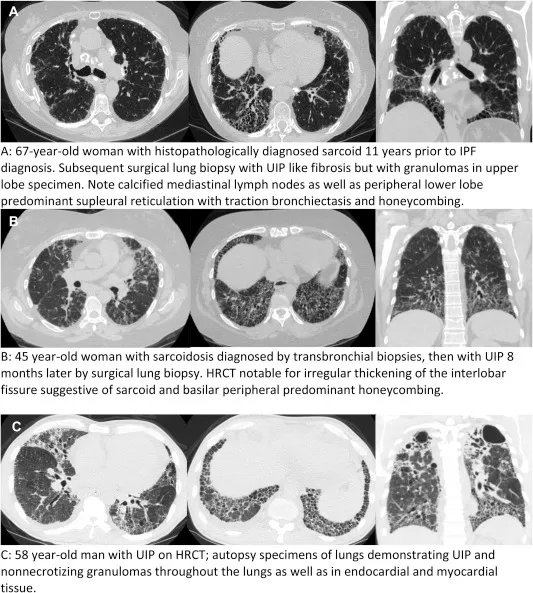

Sarcoidosis: Multisystem granuloma; common thoracic involvement.

- HRCT:

- Perilymphatic nodules (along bronchovascular bundles, interlobular septa, subpleural regions).

- Bilateral, symmetrical hilar/mediastinal lymphadenopathy (LAPs).

- Fibrosis in later stages (upper/mid zone predominant).

- Scadding Stages: 0 (Normal CXR) to IV (Pulmonary fibrosis).

Hypersensitivity Pneumonitis (HP): Immune response to inhaled antigens.

- Chronic: Fibrosis (often mid/upper zone or diffuse), honeycombing (can mimic UIP but distribution differs), significant air trapping.

- UIP Pattern (HRCT): Basal, subpleural, reticular pattern; honeycombing is hallmark. +/- traction bronchiectasis. Absence of features suggesting alternative diagnoses.

- Honeycombing: Clustered, stacked subpleural cysts (typically 3-10 mm diameter, <3 mm walls); key for UIP.